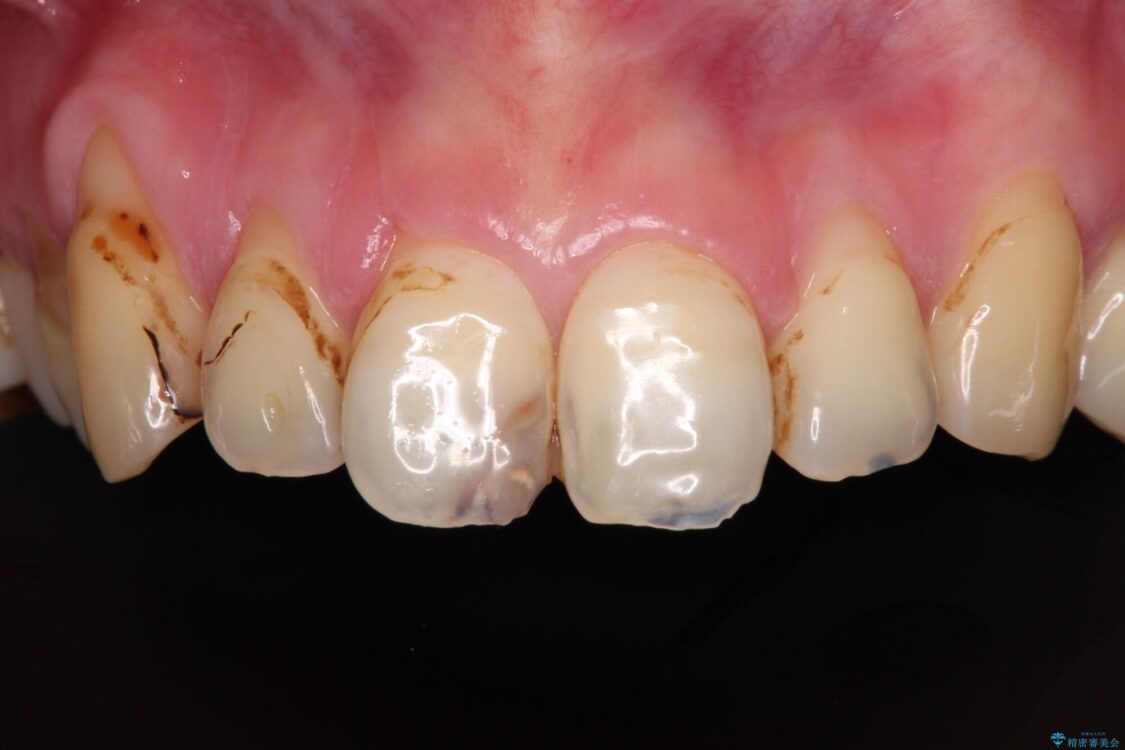

上下前歯や奥歯の虫歯治療を希望して来院された患者様です。

全顎的にむし歯が多く、根管治療の必要な奥歯や、審美的に気になっている前歯を中心にオールセラミッククラウンにて補綴治療を行うこととしました。

上顎前歯は歯肉退縮により歯根が露出していたため、事前に歯肉移植術により根面被覆を行い、その後にオールセラミッククラウンを装着することとしました。

治療前

• むし歯だらけの前歯をオールセラミッククラウンできれいに 治療前画像